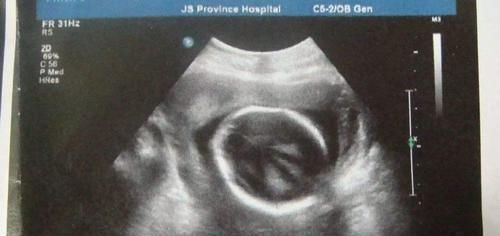

孕妈们|通过产检B超单的“肾盂分离”,可判断胎儿性别还真有一定道理

通过产检B超单的“肾盂分离”,可判断胎儿性别?还真有一定道理

肾脏与输尿管所连接的地方,便是“肾盂”。这块地方,如果没有完全连接在一起,那么便称为“肾盂分离”。

肾盂之所以会分离,主要是因为肾脏里面有积水。从胎儿的身体构造上来说,男胎儿更容易出现“尿滞留”的现象,所以,男宝宝出现“肾盂分离”的概率会更大。也因此,有些人会将此,作为判断胎儿性别的依据。

只不过,这只是概率问题,准确率大概在70%左右,而非100%。因此,孕妈或者家人,可以将此视为一种娱乐性的判别方法,但是不能抱太大希望,毕竟还有剩下30%的概率。

“肾盂分离”和其他产检数据一样,是有范围的。一般来说,胎儿的分离数据不超过10mm,新生儿的分离数据不超过16mm。在数据范围内,孕妈们基本不用担心。